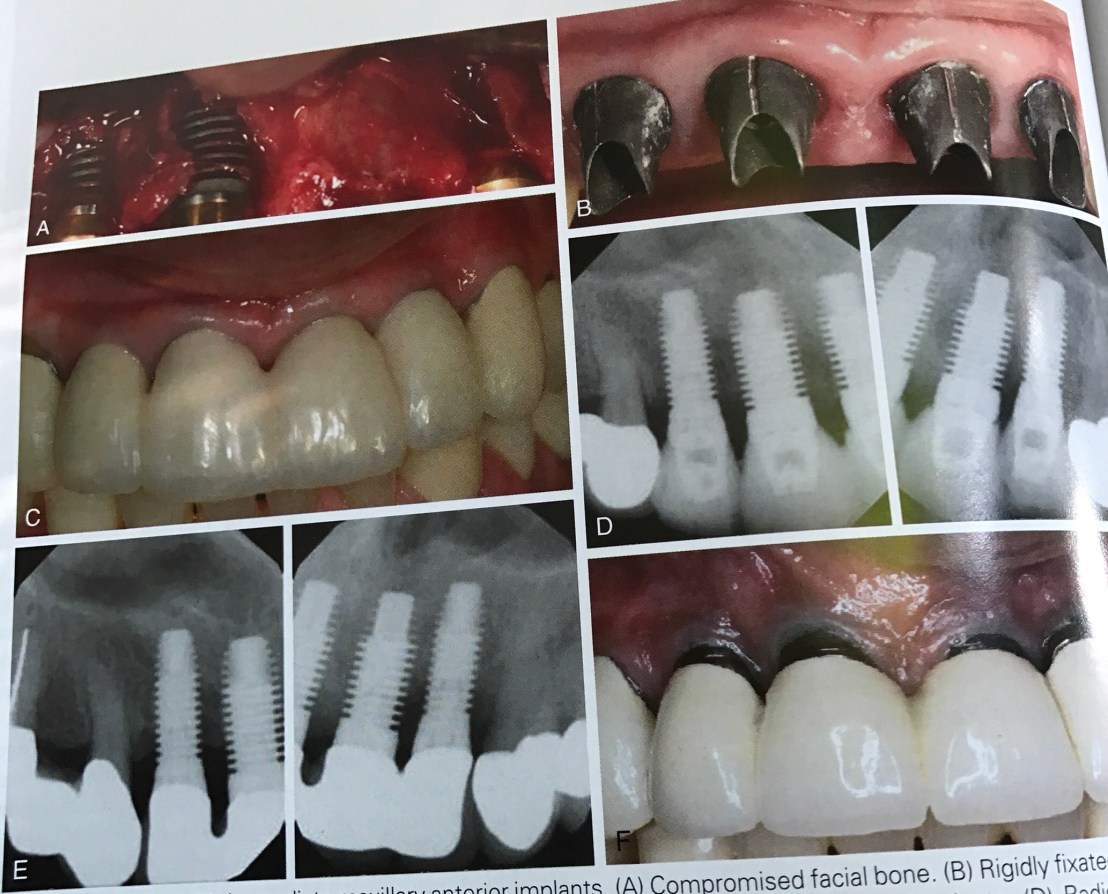

รูปแสดง Compromised Facial bone แม้หลัง Surgery เราจะได้ Attached gingiva พอ แต่หลัง F/U ไป 7 ปี พบ Crestal bone loss ดังแสดงใน Film รูป E (เทียบกับรูป D คือ X-ray ในขณะใส่ Provisional Pros)

หลัง F/U 7 ปี พบ Gingival recession

ความสำคัญของรูปนี้คือ การบอกสิ่งที่คนไข้อาจต้องเจอในอนาคตถ้าเลือกการทำ Immediate (แทนที่จะทำแบบ Delay ตามปกติ คือ การแผนการทำ Bone Graft แล้วรอเวลา) แม้ในช่วงแรก ผลออกมาเป็นที่น่าพอใจ (มี attached gingiva เพียงพอ และ Bone loss ในช่วงแรกดูปกติ) ถ้าในอนาคตเกิดผล Final อย่างที่เห็น จะทำใจยอมรับได้